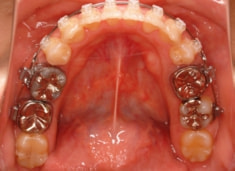

治療開始時

治療開始から約1年2ヶ月後